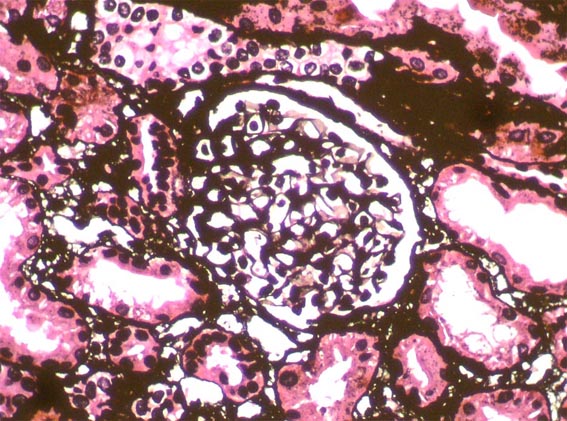

The patient is a 4-year-old girl who presented nephrotic syndrome in the first year of life, with biopsy in which focal segmental glomerulosclerosis was diagnosed. There was no response to multiple treatments. Molecular studies were unable to detect a specific genetic alteration. He developed ESRD at 3 years of age. She was in hemodialysis few months and was transplanted from a dead donor. Nephrectomy of a native kidney was done. Before the transplant, on dialysis, she had low urine output and non-nephrotic proteinuria without hypoalbuminemia or dyslipidemia. After transplantation presented progressive increase in proteinuria. Four post-transplant weeks there was complete nephrotic syndrome with proteinuria >100 mg/m2/h, dyslipidemia and hypoalbuminemia. Serum creatinine 0.5 mg/dL.

A renal biopsy was done, see the images.

Figure 6. Methenamine-silver, H&E, X400.